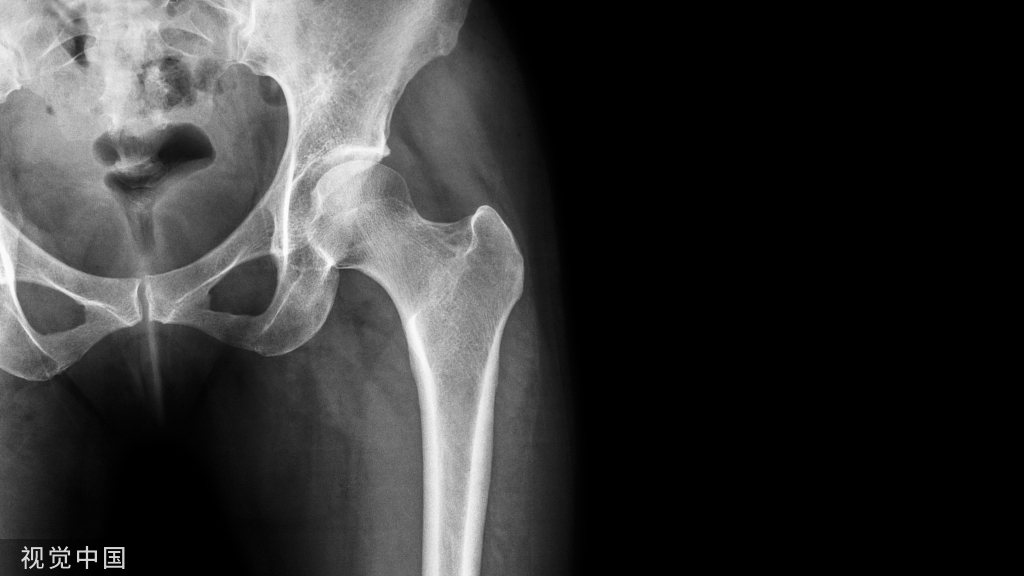

说到髌骨脱位,首先就要了解髌骨,髌骨是人体最大的籽骨,倒三角状位于膝关节前方,它的上缘与股四头肌腱相连,下缘通过髌韧带止于胫骨结节上,两侧为股四头肌扩张部,髌骨后方的凸面为光滑的关节面,与股骨下端内外髁之间的滑车凹面关节面形成关节。尽管股四头肌中的股直肌、股中间肌、股外侧肌的作用方向与髌韧带不在一条直线上,髌骨有向外突出的倾向,但因股内侧肌有向内上方牵拉作用力而使髌骨维持在正常位置。

DR检查包括下肢全长正位片、侧位片、膝关节正侧位、髌骨切线位等,有助于评估膝关节力线及滑车的形态,髌骨高度、髌骨倾斜,关节病等信息。